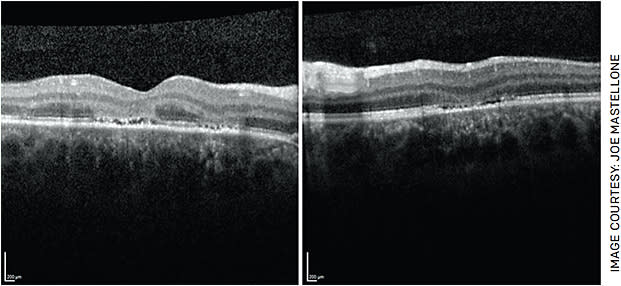

- OCT of the macula, which revealed patchy hyperreflectivity of the outer nuclear layer with loss of the ellipsoid zone in the fovea and inferior to the fovea in the right and left eyes, respectively (Figure 2).

FIGURE 2. Optical coherence tomography (OCT) of the macula OU demonstrating focal areas of hyperreflectivity involving the outer nuclear layer with loss of the underlying ellipsoid zone in the right eye (left image). There is overlying depression of the inner retinal layers in the left eye (right image). - Fundus autofluorescence (FAF), which demonstrated patchy areas of hyper-autofluorescence in the fovea OD and inferior to the fovea OS (Figure 3).

Our case presented with classic findings of APMPPE: a young patient with a preceding viral prodrome, rapid onset central scotoma OD and bilateral placoid lesions. Our patient was treated with 60 mg of prednisone for 3 days followed by 40 mg daily. Over the next 2 weeks, visual acuity improved from 20/100 to 20/30 in the right eye. Visual acuity remained 20/20 in the left eye despite the presence of lesions likely due to the sparing of the fovea. Repeat OCT macula demonstrated reconstitution of the ellipsoid zone and improving hyperreflectivity of the outer nuclear layer (Figure 4). Repeat FAF showed decreasing hyper-autofluorescence (Figures 5A and 5B). With time, the lesions are expected to become hypoautofluorescent due to RPE atrophy. Repeat fundus photos after 2 weeks showed decreased retinal whitening and increased subretinal pigmentation within the area of the lesions in both eyes (Figures 5C and 5D).